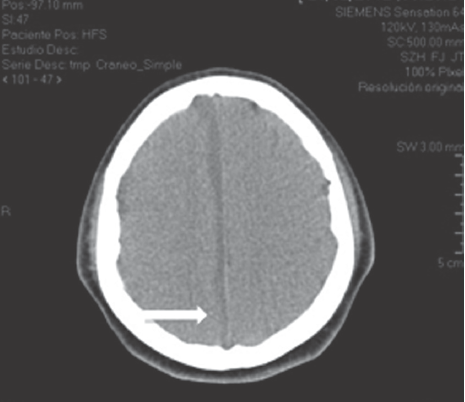

La biometría hemática reportó hemoglobina 13.1 q/dL; hematocrito 39.3%; leucocitos 12,500/μL; neutrófilos 81%; linfocitos 17%; plaquetas 601,000/μL, proteína C reactiva 5.2 mg/ dL. Una tomografía axial de cráneo mostró un absceso cerebral frontal izquierdo (Figura 1).

Figura 1 A) Sinusitis con extensión etmoidal (flecha). B) Lesión anular hipodensa en la sustancia blanca lobar frontal izquierda con diámetros de 3 x 3 cm y aerocele menor a 1 cm3 sugerentes de absceso cerebral frontal izquierdo (flecha delgada). Edema perilesional y discreta compresión del asta frontal del ventrículo lateral izquierdo sin desviar estructuras de la línea media (flecha gruesa), sin comunicación a ventrículos ni al espacio subaracnoideo.